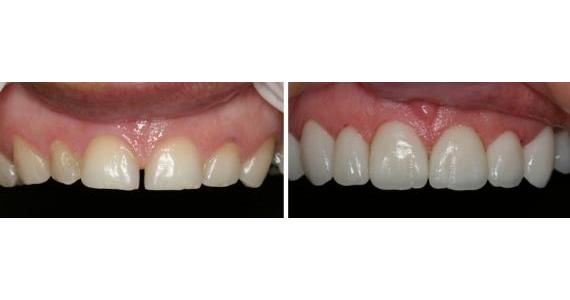

Carga Imediata

Para muitos pacientes, a necessidade de estar sem a prótese durante um período de tempo, após a instalação dos implantes, pode ser considerada inconveniência em função do convívio social e atividades profissionais. O termo carga imediata pode ser definido como instalação de implantes osseointegrados em condições ideais à estabilidade primária, seguida de ativação protética ( colocação dos dentes ) 48 horas após a cirurgia. Esta definição era aplicada à instalação de múltiplos implantes dentários e a contenção entre os mesmos promovendo um efeito de estabilidade. Com estudos recentes podemos colocar o implante unitário e colocar o dente no mesmo instante, sendo observado somente uma boa estrutura óssea.

Podemos prever o resultado ?

Observando o estudo comparativo entre a técnica convencional estabelecida por BRANEMARK e o protocolo de carga imediata temos como grandes vantagens a diminuição do tempo das consultas e a rapidez dos resultados oferecidos ao paciente, com efeito psicológico e social melhorados, já que os resultados geram bem estar funcional e estético. Os pacientes devem ser selecionados e a indicação estabelecida após controle sistêmico da saúde e das condições locais favorecidas para essa técnica. Comparada com a técnica convencional onde o paciente esperaria normalmente de 3 a 6 meses para a colocação dos dentes, a técnica da carga imediata pode ser uma ótima opção.